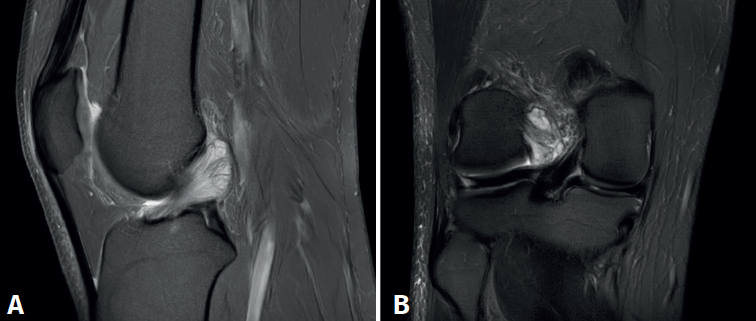

reaca.32385.fs2409018-figura5.png

Figura 5. Visión artroscópica desde el portal anterolateral. A: tras el desbridamiento se observa que no existe pinzamiento del espacio articular femorotibial lateral en posición “de cuatro” a 90° de flexión; B: palpación de la tensión del remanente del ligamento cruzado anterior.